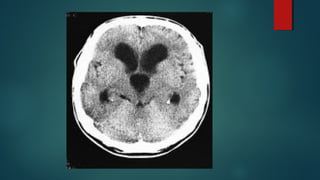

Este documento es el programa para un taller de imágenes del curso de emergencia 2015 impartido por el Dr. Víctor Delgado. El taller se centra en el uso de imágenes médicas para el diagnóstico y tratamiento de pacientes en coma traumático según la base de datos de Marshall. El Dr. Delgado es el único instructor repetido a lo largo del documento.